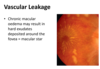

True or false - vascualr leakage results in retinal oedema?

True

How can hard exudates form?

From vascular leakage

What are hard exudates and what do they look like on the fundus?

Lipo proteins that have been released ( from vascualr leakage).

They have a yellow waxy appearance on the fundus.